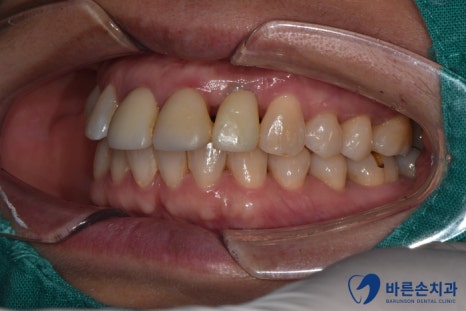

상실된 어금니와 함께

앞니 임플란트가 완료 되었습니다. !

정상적인 위치에 자리잡은 치아가 보이시나요?!

원래 내 치아처럼 회복되었습니다!

앞니 부분 잇몸이 크게 내려가지 않아,

주변 치아들과 이질감이 없습니다.